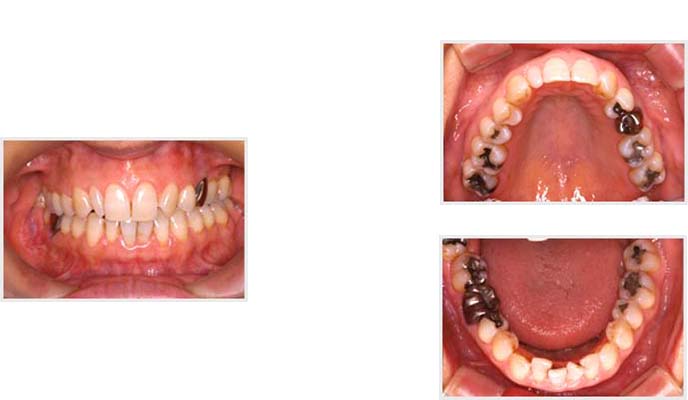

処置前

治療後

こちらは60代女性の方のお口の中の写真です。

治療前後で、明らかにお口の中がキレイになっているのがお分かりでしょうか?

この方は、ご自身のお口の中に興味を持たれ、今の自分のお口の中の状況をしっかりと理解し、もっともっとキレイにしたい!と、治療を熱心に行われた方です。